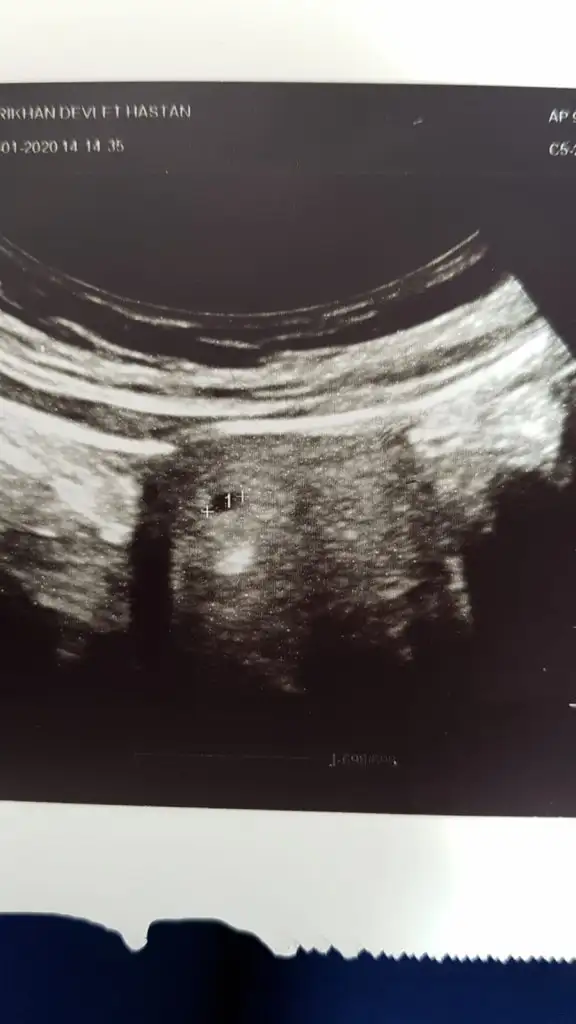

Bugünde üstten bakınca 1 alttan bakındica 3 kese gördü doktor ama çok yavaş gelişiyor dedi